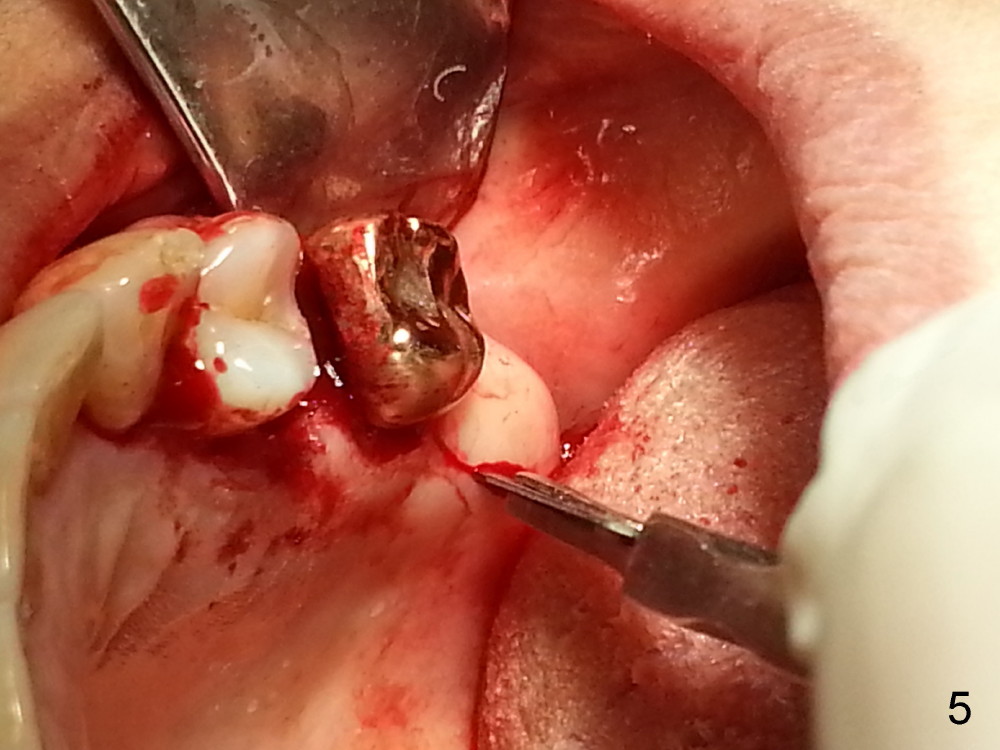

Grafting Following Immediate Implant (Photos Provided by Xue Steven, DDS)

The tooth #13 appears to be affected by periodontits and occlusal trauma (Fig.1*). After using a periotome (Fig.2), the tooth is extracted (Fig.3). The buccal flap is raised (Fig.4). Gingival graft is to be harvested from the site of #15 (Fig.5). The tissue is elevated buccally (Fig.6) and separated (Fig.7). The donor site is covered by a collagen membrane (Fig.8*). A diamond bur is used to induce bleeding from the socket (Fig.9*). Osteotomy is initiated (Fig.10) and enlarged (Fig.11,12). A tapered implant is being placed (Fig.13-15) following internal sinus lift (Fig.16,17). The implant is placed subcrestally, followed by bone graft (Fig.18), soft tissue graft (Fig.19), and suturing (Fig.20 <, Fig.21).